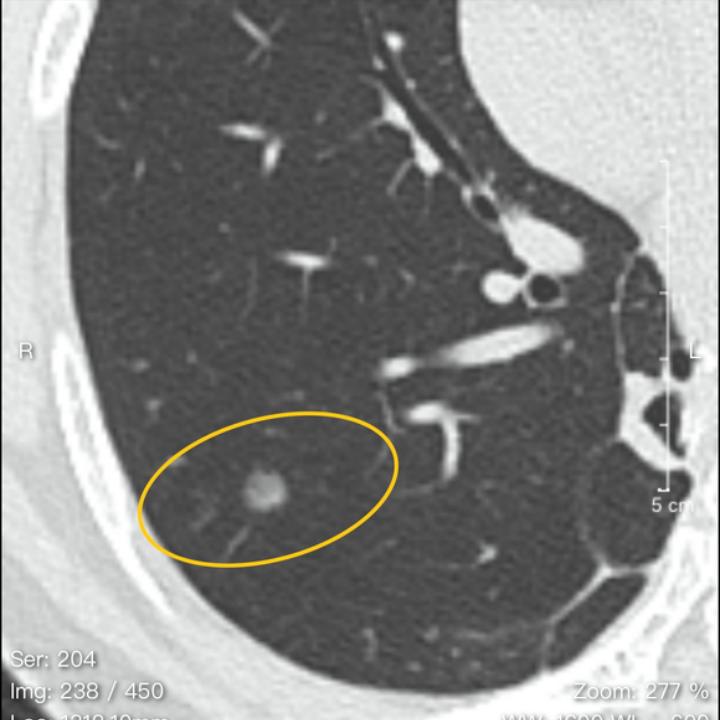

今天的这位结友,2020年初发现右肺的磨玻璃结节和“实性结节”(这里实性结节我打了引号,因为当时医生出现了判断失误,把混磨看成了实性结节)。2021年4月手术切除了磨玻璃结节,但在后期的复查,留下的“实性结节”始终无法精准诊断。到了今年,结节长大,当地医院忽然又建议手术。这可吓坏了这位结友,好好地咋忽然又要手术了?

于是来贴吧找我,希望我给个精准诊断。从片子上看来,这个混磨已经发展成微浸润腺癌或浸润性腺癌的状态,还可能需要手术。

女,51岁,工作环境良好。2020年元月体检发现右肺1.2cm磨结和5mm实性结节,2021年4月切除大磨,1A1期。5mm实性小结节随访,其间有消炎和服中药2年,多次复查改报磨结,今年4月复查CT提示长大了,门诊意见可随诊可切除,令人不知所措,心忧不已。

这哪是实性结节?接近实性结节而已,典型的混磨,第一次次手术大小兼顾,带掉就好了。

至少微浸润腺癌,楔形切除小手术还可以根治。